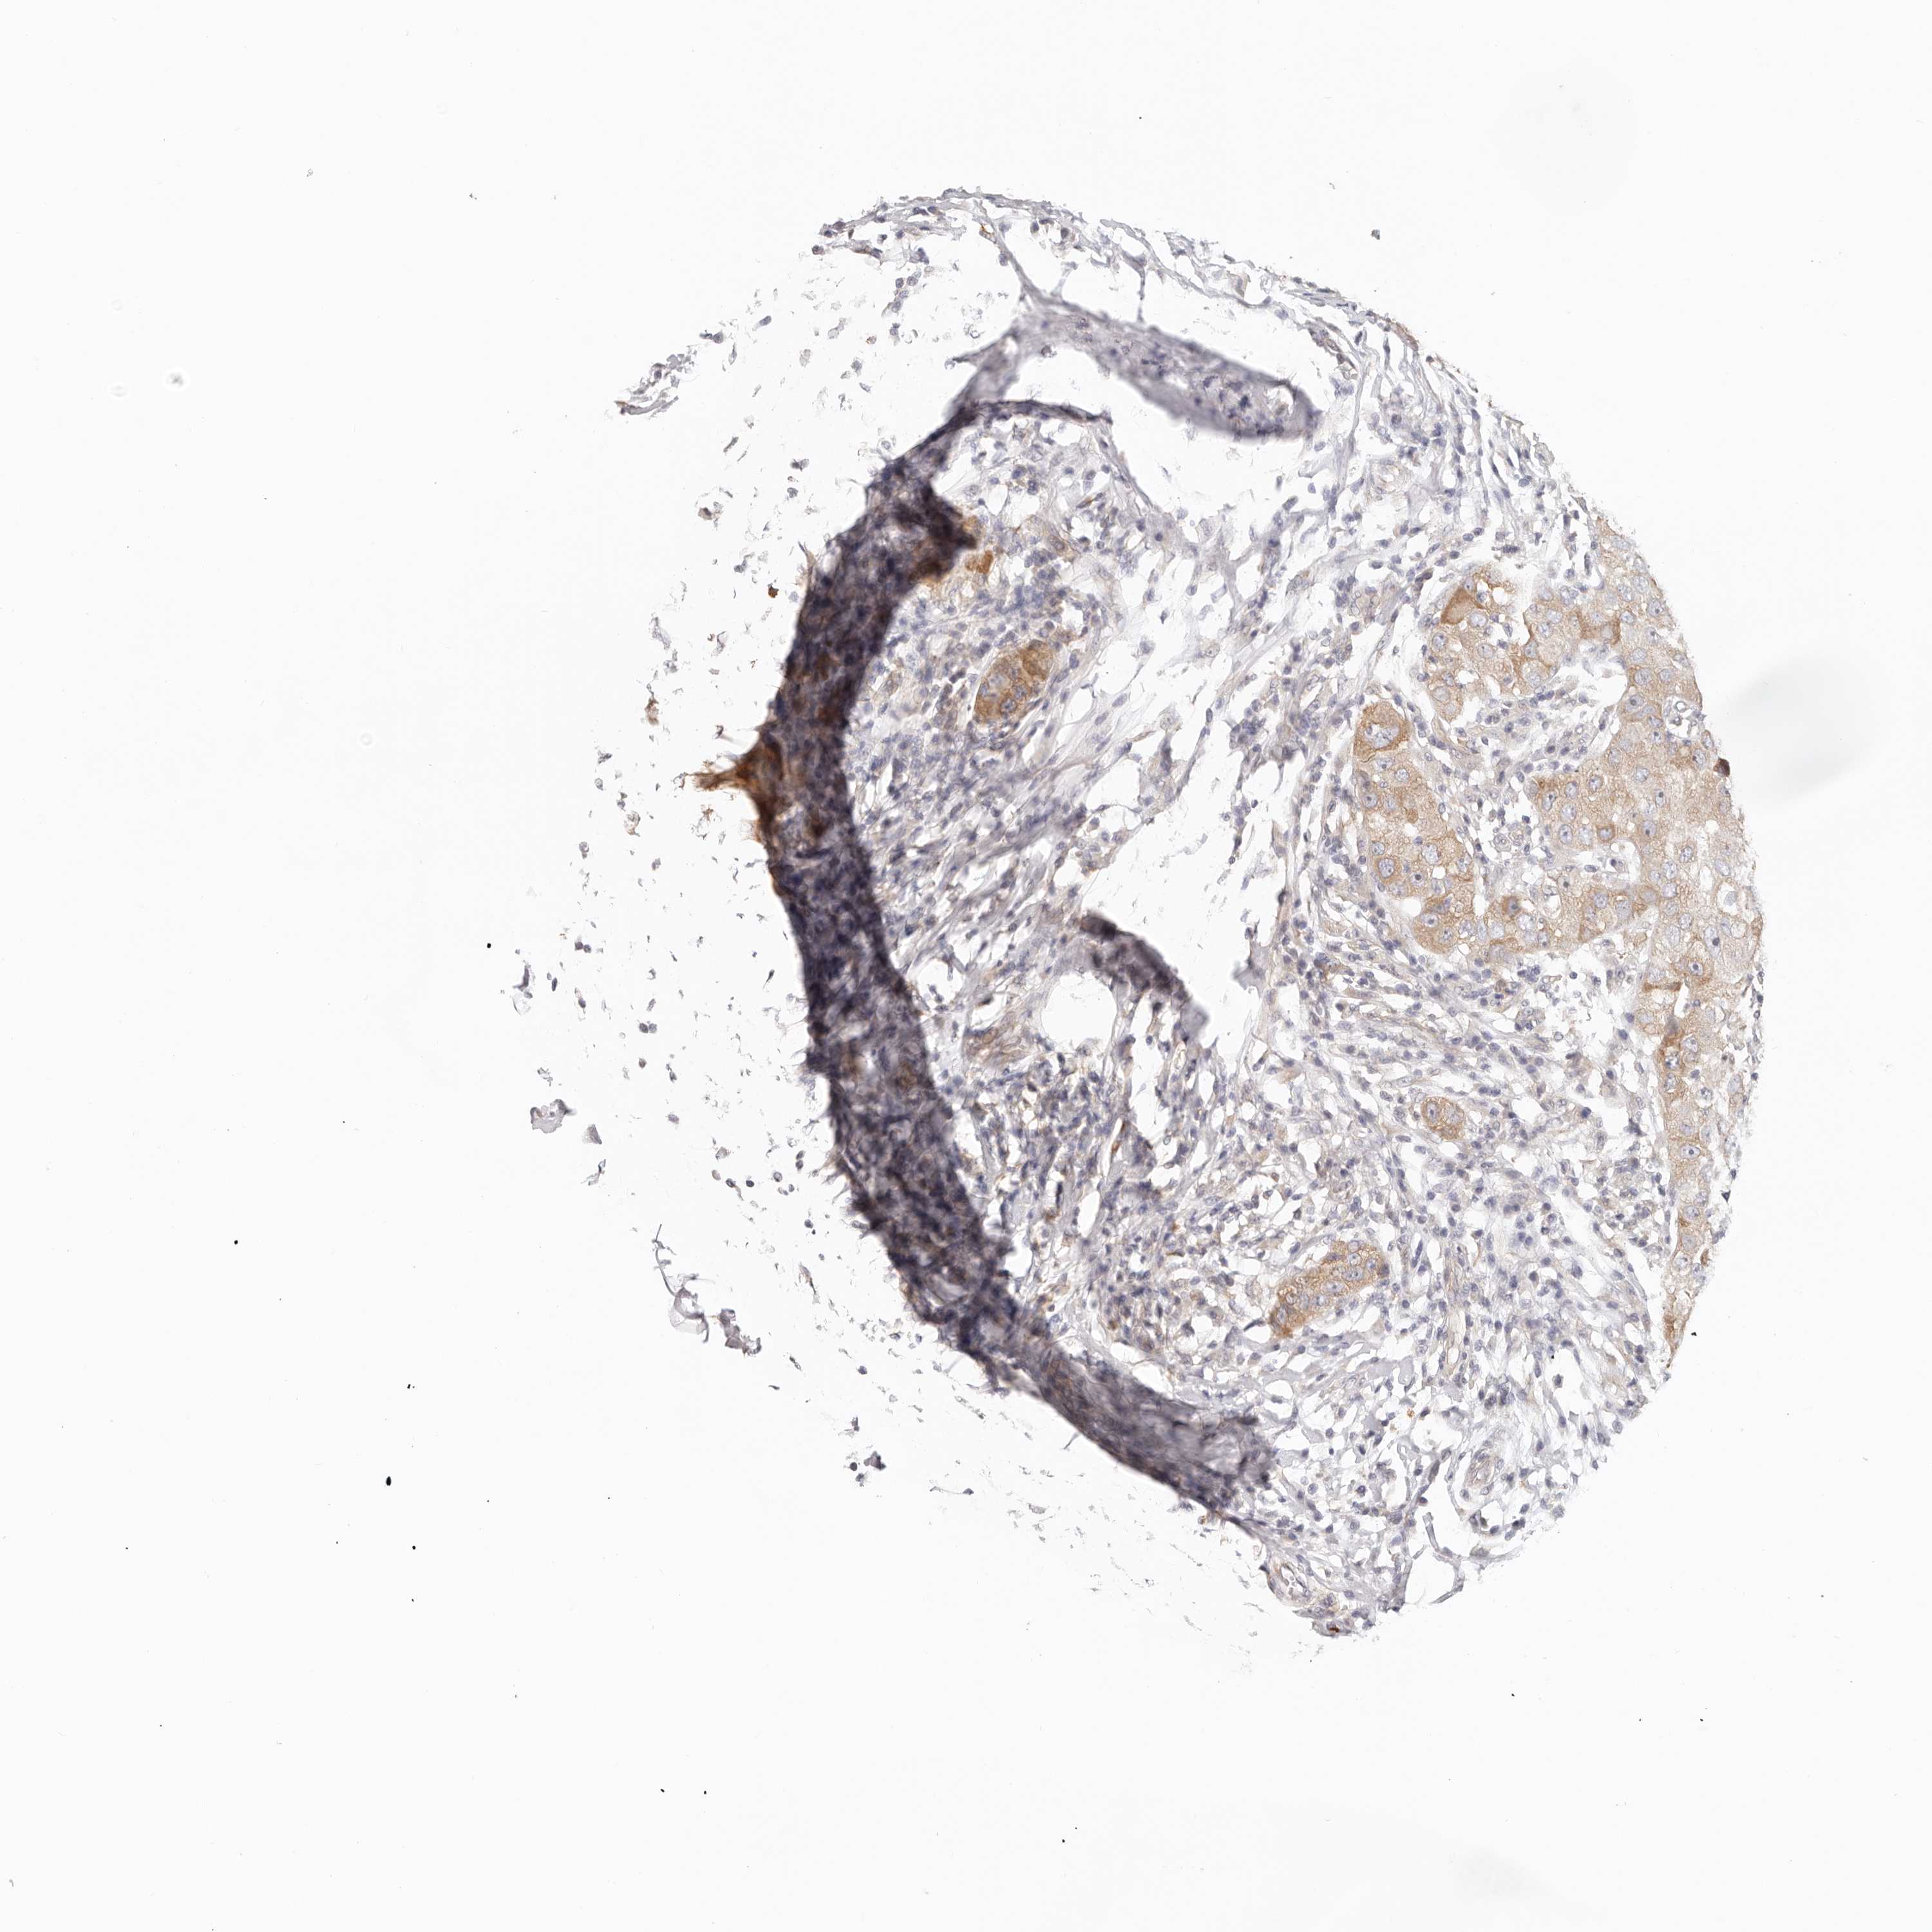

BRCA TCGA BRCA VALIDATION PROTEIN EXPRESSION

ANTIBODIES

AND

VALIDATION